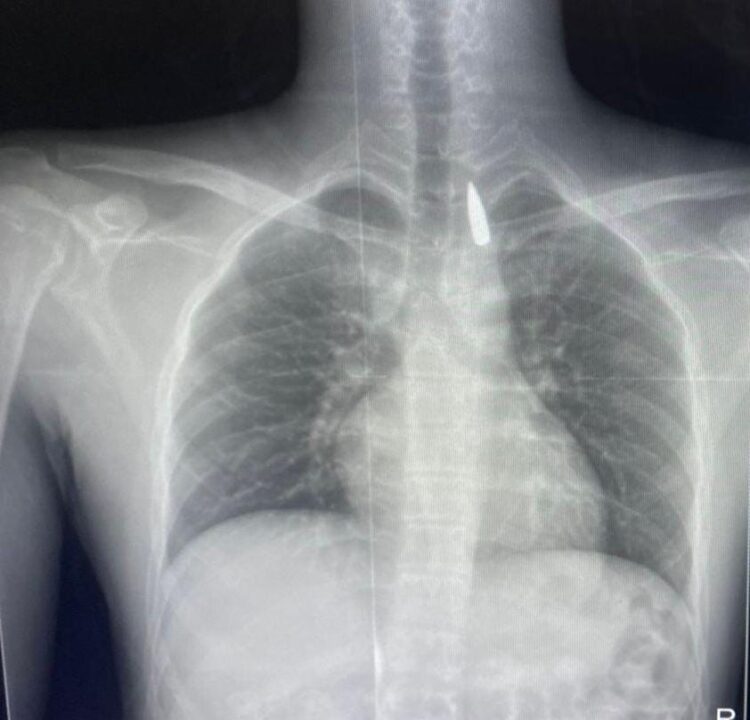

وأوضح الدكتور تامر عبد الله، عميد كلية الطب ورئيس مجلس إدارة المستشفيات الجامعية، أنه في يوم 21 أكتوبر 2025 تمكن فريق من أطباء قسم جراحة القلب والصدر والتخدير والمعاونين من إجراء جراحة دقيقة بالغة الخطورة لأحد المرضى المحجوزين من قطاع غزة،

والذي كان قد تعرض لإصابة بطلق ناري في الرأس منذ فترة، استقر المقذوف على إثرها داخل تجويف القفص الصدري قرب الشريان الأورطي، وهو أكبر وأهم شرايين الجسم والمسؤول عن تغذية جميع الأعضاء الحيوية، وأضاف أن الفريق الطبي، رغم دقة الحالة وتعقيدها، نجح في استخراج المقذوف بأمان بعد عملية جراحية نادرة استمرت عدة ساعات داخل المستشفى الجامعي الجديد،

حيث خضع المريض بعدها للرعاية الطبية اللازمة، وحالته حاليًا مستقرة وتحت المتابعة الدقيقة من الفريق المختص.